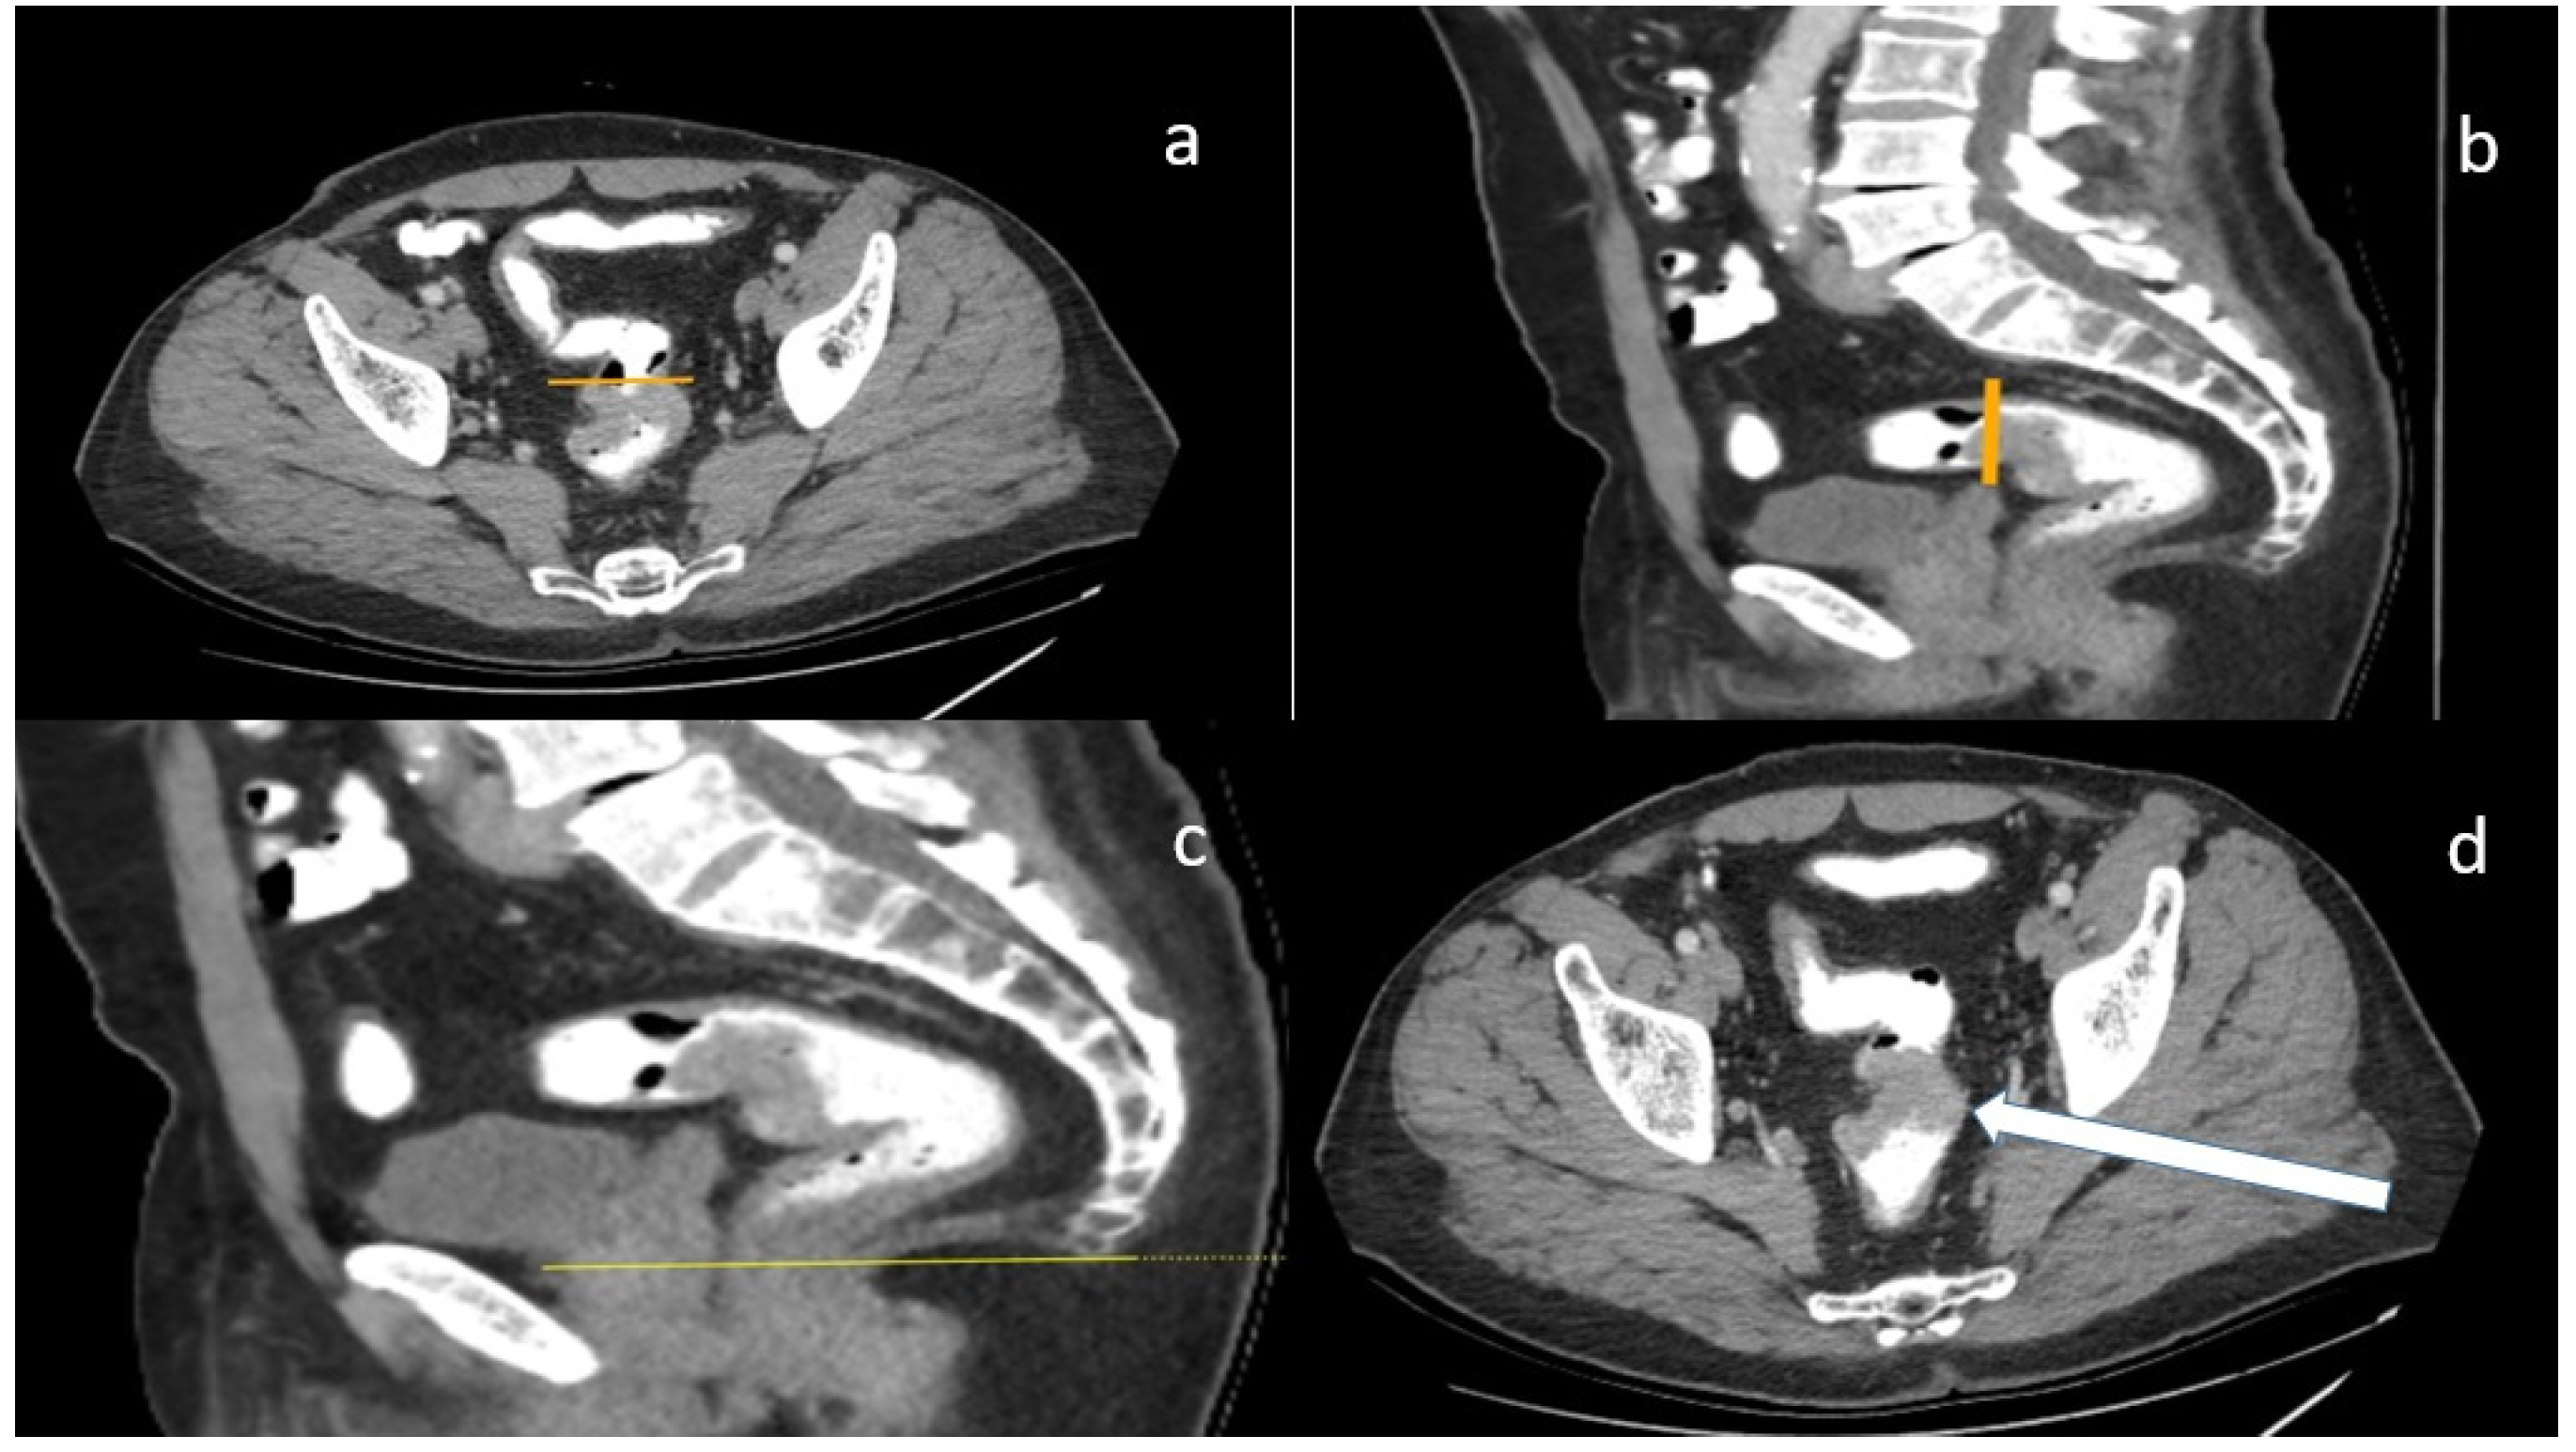

Figure 1. (a) Sigmoid take-off with axial plane (yellow line); (b) sigmoid take-off with sagittal plane (yellow line); (c) anorectal line with sagittal plane (yellow line); (d) tumor appearance with axial line (white arrow shows tumor).

The rectum, which has no haustral structures and is accompanied by the mesorectal layer, up to the rectosigmoid junction at the level of the 3rd sacral vertebra, from the anorectal angle, consists of the lower (up to 8 cm), middle (between 8–12 cm), and upper (12–15 cm) sections, all of which were examined. Sigmoid take-off was defined as the point at which the sigmoid moves horizontally away from the sacrum on the sagittal view MRI and as the point at which the sigmoid exits ventrally in the axial view. Axial, coronal, and sagittal CT images were used together to calculate the distance from the tumor to the anorectal junction. For segments that continued without angulation, the total distance was calculated by multiplying the section thickness, spacing, and number of sections, and for segments that were angulated and where a specific section was observed in a single section, this was performed by adding these distances together and measuring the entire length of the part included in the section.